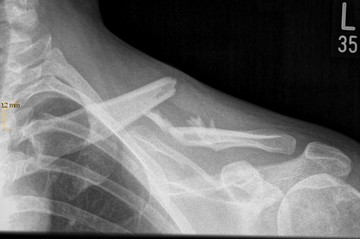

Oberarmfrakturen

Oberarmfrakturen sind häufige Frakturen der älteren Menschen. Mit der Radiusfraktur (Handgelenk), den hüftgelenknahen Frakturen und den Wirbelkörperfakturen gehören sie zu den häufigsten osteoporotischen Extremitätenfrakturen. Durch ein Sturzgeschehen mit Anprall auf den Ellenbogen oder das Abfangen des Sturzes auf die ausgestreckte Hand entsteht eine axiale Krafteinwirkung auf die Schulter, die zur Fraktur führt (Niedrigenergietrauma). Bei jüngeren Patienten sind es häufig Stürze im Rahmen von Sport- oder Verkehrsunfällen (Hochenergietrauma).

Der große Kopf des Schultergelenkes ist direkt an seinem Übergang zum Schaft des Oberarmes besonders frakturgefährdet. An dieser Stelle kommt es häufig zu Brüchen (subkapitale Humerus-Fraktur).